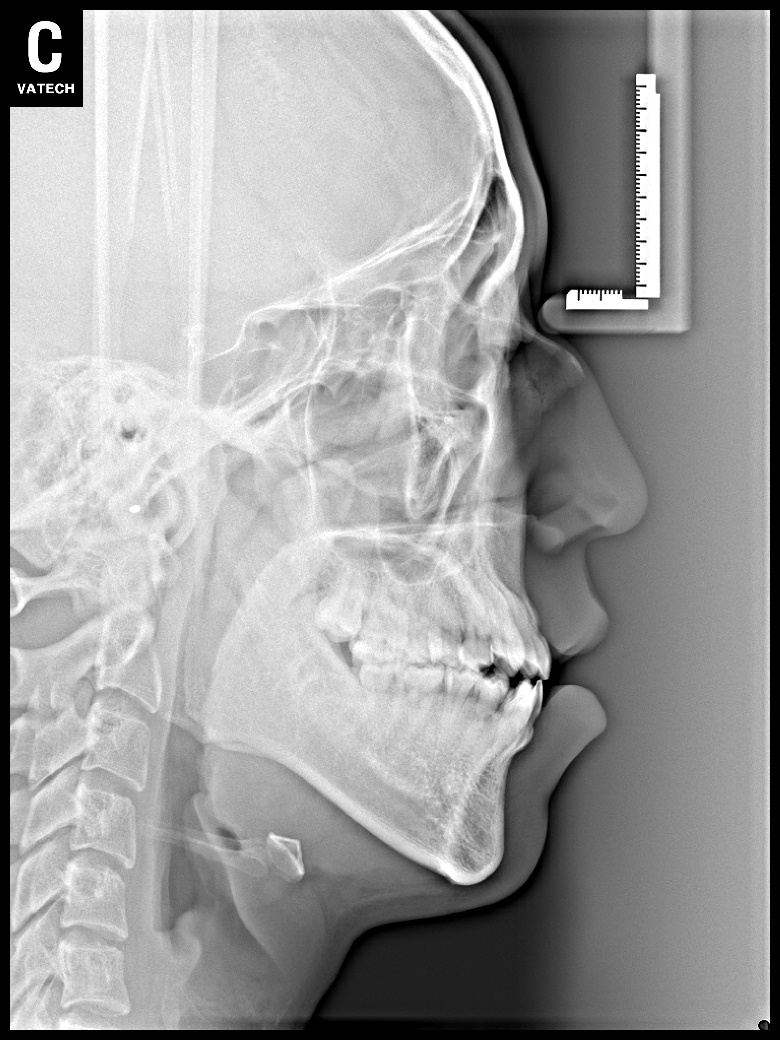

치료 후 사진입니다.